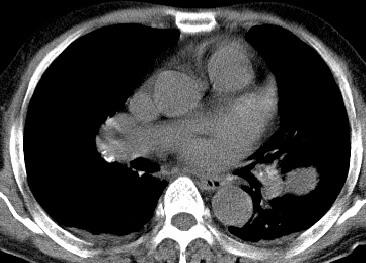

以下是引用光影相伴在2008-4-20 14:39:00的发言:[br]支持:1)左侧中央型肺癌伴左肺上叶阻塞性肺炎。、[br] 2)双侧少量胸腔积液。

以下是引用xianxianzhongyi在2008-4-20 14:44:00的发言:[br]本人愚见:次病例短短两月的时间,呈现如此大面积实变,病变增长过于迅速,此其一。其二,病变在动脉早期既有明显强化。其三,左上叶后段及下叶背段多叶受累。其四,肺门及纵隔内未见明显肿大的淋巴结。估计层面较厚段支气管显示不清。 诊断:炎性实变可能性大。